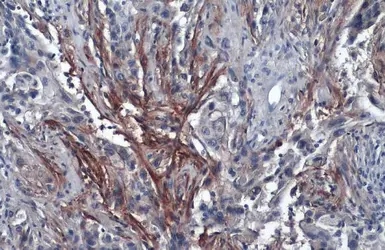

Anti-Carbonic Anhydrase IX antibody [GT12] used in IHC (Paraffin sections) (IHC-P). GTX70020

GTX70020 IHC-P Image

Immunohistochemical analysis of paraffin-embedded renal cell carcinoma (clear cell type) using anti-CAIX antibody [GT12] (GTX70020) at a dilution of 1:1000.